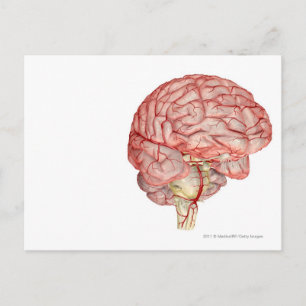

Röntgen från hjärnan inuti en skalle poster

Pris343,00 kr

Röntgen från hjärnan inuti en skalle canvastryck

Pris1 689,00 kr

Röntgen från hjärnan inuti en skalle vykort

Pris21,00 kr